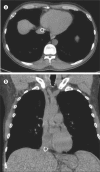

Transjugular intrahepatic portosystemic shunt (TIPS) extension far into the inferior vena cava (IVC) or the right atrium may complicate or preclude orthotopic liver transplantation depending on the space available for placement of a hemostatic clamp in the suprahepatic IVC. Until 2004, most TIPS were performed with bare metal stents, which integrate into the vessel wall, making percutaneous or intraoperative repositioning uncertain. Most TIPS are currently created with stent grafts that have an outer fabric to increase shunt patency and prevent endothelial ingrowth. We describe the first known manipulation of a covered stent graft prior to transplantation. The stent graft, which extended well into the IVC, was snared from a femoral approach and deflected caudally in order to document feasibility and nonadherence to the vein wall prior to definitive surgical planning of liver transplantation. Provisions were made for endovascular retraction during actual transplant surgery 9 weeks later, but this became unnecessary when manual retraction of the exposed liver enabled suprahepatic IVC clamping. Due to the nonadherent nature of the outer graft material, compared with a bare metal stent, extension of a stent graft into the IVC or right atrium may not preclude transplantation, and intraoperative endovascular retraction may be considered.